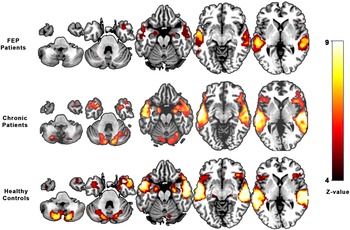

Patients with FEP showed activation during the emotional word task in the bilateral middle temporal (BA 21), bilateral hippocampus (left, BA 28; right, BA 35), right inferior orbitofrontal (BA 47), and left cerebellum (Table 3 and Figure 1).

Figure 1. Brain activation during emotional auditory paradigm in first-episode psychosis patients, chronic psychosis patients, and healthy controls.

HCs showed a similar pattern of activation, including the bilateral middle temporal (BA 21), left inferior temporal (BA 20), bilateral cerebellum, left precentral (BA 6), right supplementary motor area (BA 6), left superior frontal (BA 32), left putamen (BA 48), and right hippocampus (BA 20) (see Table 3 and Figure 1).

Chronic patients mainly activated the right middle temporal (BA 21), left superior temporal (BA 21), bilateral inferior frontal (left, BA 44; right, BA 45), bilateral cerebellum, bilateral precentral (left, BA 06; right, BA 44), left insula (BA 47), right hippocampus (BA 20), and right frontal inferior gyrus (BA 38) (see Table 3 and Figure 1).

Compared with control subjects, FEP patients did not show any differences in activation, with FWER <0.05. However, using a liberal threshold (uncorrected p < 0.001), they showed hypoactivation in the right temporal lobe (BA 21). Similarly, the inferior frontal gyrus (bilateral) showed a significant reduction in activation in FEP patients when compared with chronic patients (uncorrected p < 0.001) (BA 44, BA 45) (Table 3).

Three main findings resulted from the present study. First, this study provides an image comparison of FEP patients to HCs and found reduced activity in the bilateral temporal cortex (mainly on the right side). Functional studies about emotional processing in HCs have differentiated successive steps (auditory analysis and evaluative judgments) of cerebral processing involving auditory analysis within the temporal lobe [Reference Schirmer and Kotz25, Reference Wildgruber, Ackermann, Kreifelts and Ethofer26].

Second, interestingly, the CHrP group showed the opposite, greater activation in the bilateral superior temporal lobe than HCs and FEP patients during the processing of emotional words. These results suggested that the temporal lobe plays a critical but complex role in the pathogenesis of psychosis. The auditory cortex has been reported to play a pivotal role in the processing of affective prosody [Reference Wildgruber, Ackermann, Kreifelts and Ethofer26, Reference Sander, Grandjean, Pourtois, Schwartz, Seghier and Scherer27].

We observed a decrease in activation in the right middle temporal lobe in the FEP group. This finding is in accordance with the assumption that this area subserves the representation of meaningful prosodic sequences in the processing of emotional words and suggests that abnormal processing of emotional words in FEP patients was conducted in the limbic system rather than in the auditory cortex [Reference González-Vivas, Soldevila-Matías, Sparano, García-Martí, Martí-Bonmatí and Crespo-Facorro6].

In this sense, our results confirm that middle temporal functional alterations in FEP patients represent one key neural factor in the pathophysiology of psychosis. Considering that when HCs’ enhanced brain activity is involved, it is predominantly the temporal cortex, and passive listening to speech with prosody-caused activation relies on the right temporal cortex [Reference Woodruff29, Reference Mwansisya, Hu, Li, Chen, Wu and Huang30].

Activation in the temporal lobes is shown (Figure 1), corresponding to the expected stimulation of auditory brain areas by the auditory paradigm used during the scan. These findings matched the images obtained from HCs. Hyperactivity in the temporal areas was observed, matching the images obtained from chronic psychotic patients in previous studies [Reference Sanjuan, Lull, Aguilar, Martí-Bonmatí, Moratal and Gonzalez16, Reference Martí-Bonmatí, Lull, Garcia-Martí, Aguilar, Moratal-Pérez and Poyatos18, Reference Escartí, de la Iglesia-Vayá, Martí-Bonmatí, Robles, Carbonell and Lull19]. This established a link between enhanced activity in emotional and temporal processing regions [Reference Martí-Bonmatí, Lull, Garcia-Martí, Aguilar, Moratal-Pérez and Poyatos18, Reference Escartí, de la Iglesia-Vayá, Martí-Bonmatí, Robles, Carbonell and Lull19, Reference Modinos, Tseng, Falkenberg, Samson, Mcguire and Allen31] and their centrality in the pathophysiology of psychosis symptoms as a continuum of brain changes.

Although neuroimaging studies have revealed alterations in emotional processing [Reference Green, Bearden, Cannon, Fiske, Hellemann and Horan34] and social functioning [Reference Valmaggia, Stahl, Yung, Nelson, Fusar-Poli and McGorry35] in FEP patients, as well as enhanced brain activity in chronic patients [Reference Sanjuan, Lull, Aguilar, Martí-Bonmatí, Moratal and Gonzalez16], our results provide the first evidence that activation under an emotional auditory paradigm during fMRI in FEP patients was decreased in the bilateral temporal lobes compared with HCs. This attenuation of the response to emotional auditory stimuli may be a key neurobiological mechanism associated with clinical manifestations in the early stages of psychosis. The greater activation of the temporal lobe in CHrPs might be the result of emotional memory with a key role of the amygdala and hippocampus [Reference Escartí, de la Iglesia-Vayá, Martí-Bonmatí, Robles, Carbonell and Lull19].